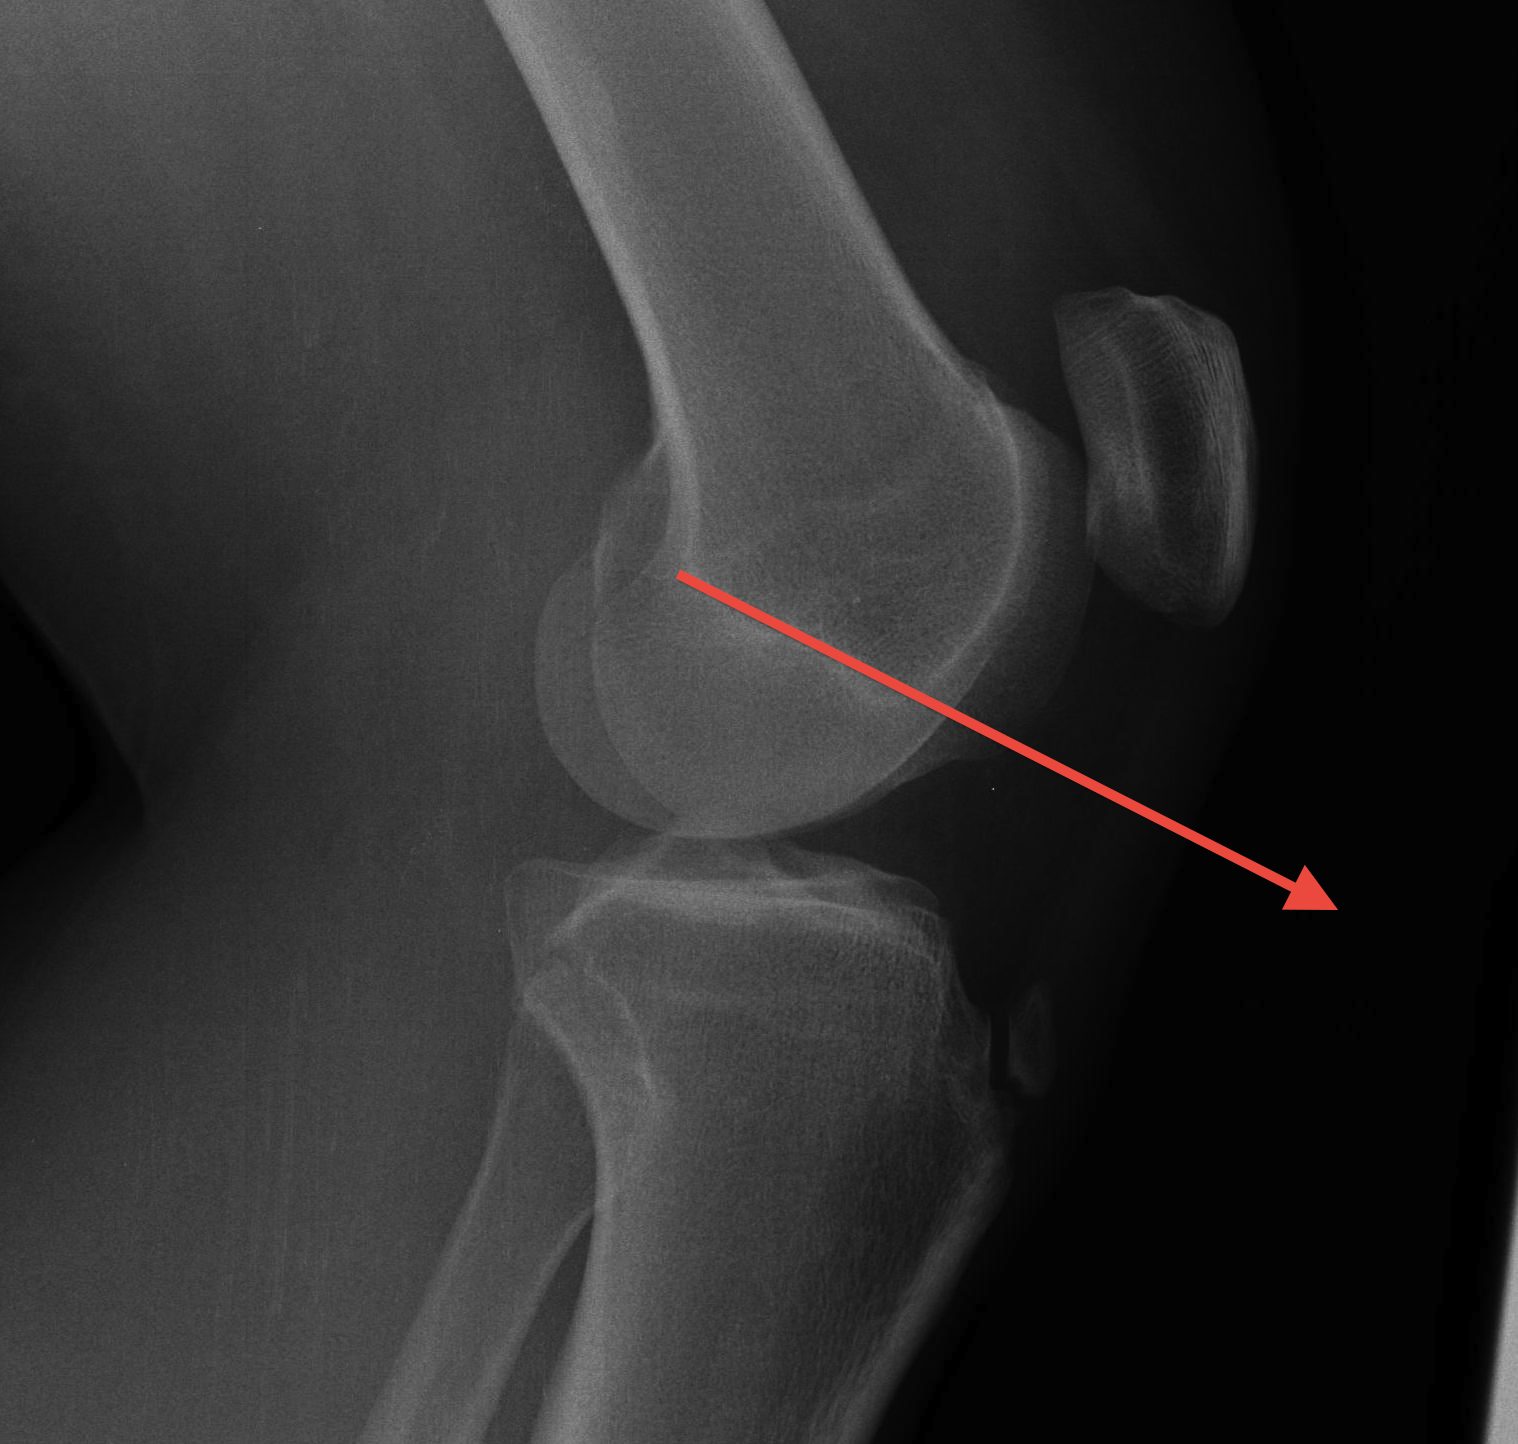

B. Blackburn-Peele ratio / Best and Most accurate

Distance between tibial and patella articular surface

- divided by patella articular surface

- patella alta > 1